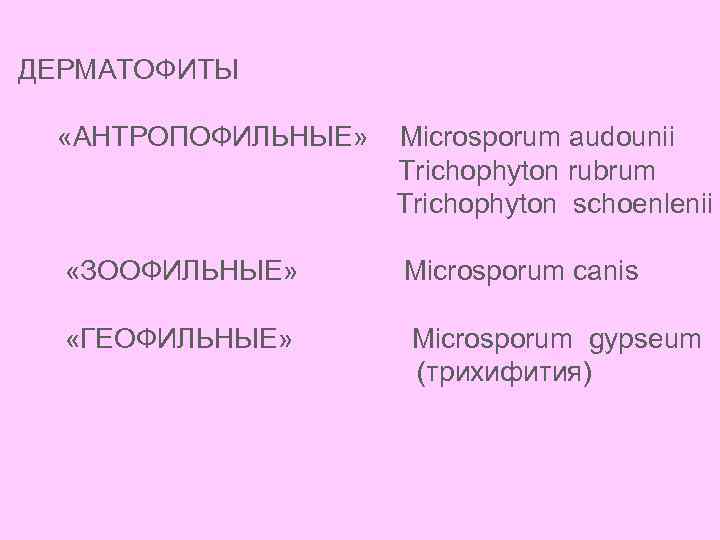

ДЕРМАТОФИТЫ «АНТРОПОФИЛЬНЫЕ» Microsporum audounii Trichophyton rubrum Trichophyton schoenlenii «ЗООФИЛЬНЫЕ» Microsporum canis «ГЕОФИЛЬНЫЕ» Microsporum gypseum (трихифития)